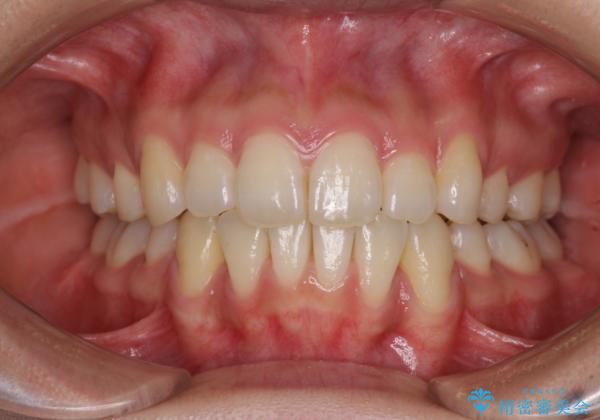

- 以前の矯正治療の後戻りにより、上下の前歯がでこぼこになってしまったことを気にして来院された患者様です。

口元がこれ以上突出することなく前歯の叢生が改善できるよう、歯と歯の間を削ってスペースを獲得し、インビザラインを用いて整えていくこととしました。

目安の装着時間である1日22時間をしっかりと実践してくださり、半年強という短期間で治療を終えることができました。